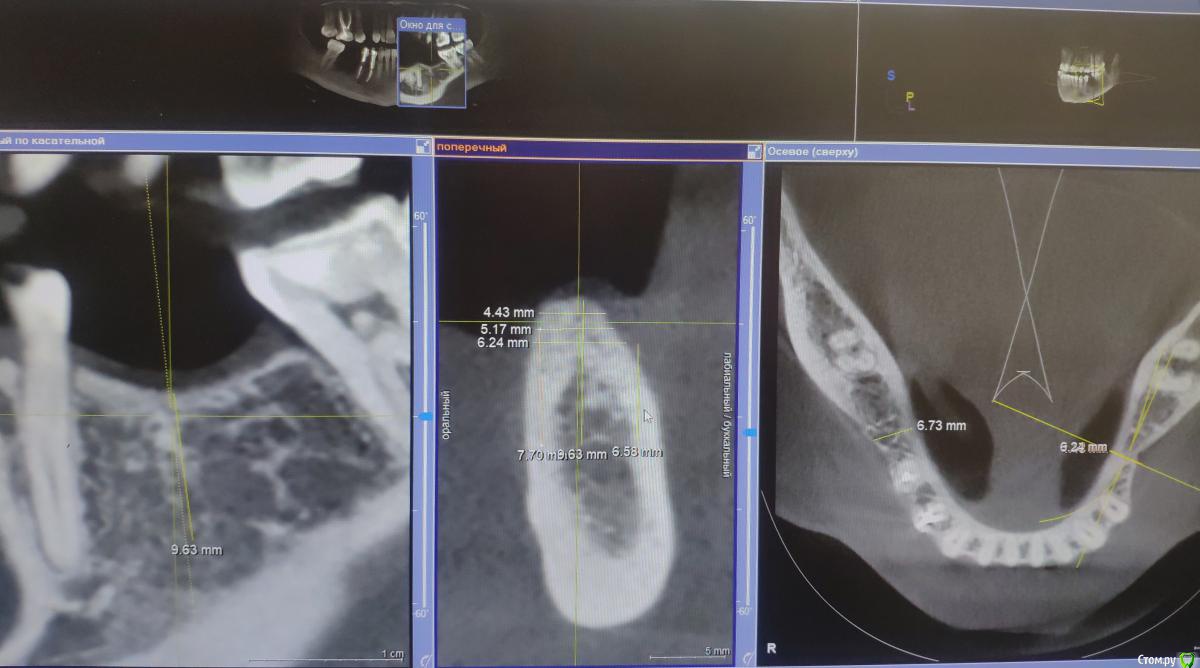

Fin Опубликовано 29 июля, 2020 Поделиться Опубликовано 29 июля, 2020 Здравствуйте коллеги. У пациента отсутствуют зуб 3.5 и 3.6. и высоко расположенный канал тройничного нерва. Что бы вы сделали в данном случае? Наращивать ширину? Ставить ССТ? Ссылка на комментарий

annda Опубликовано 3 августа, 2020 Поделиться Опубликовано 3 августа, 2020 (изменено) Стоял до этих имплантатов суперлайн коротыш 7мм,одиночка.Заколебались с раскруткой винта,ходила каждый месяц.Плюнула,решили выкрутить,переставить на эти.КТ после удаления. Изменено 3 августа, 2020 пользователем annda 1 Ссылка на комментарий